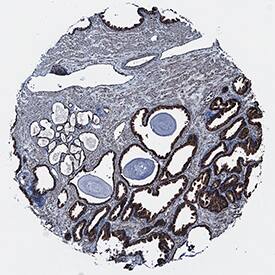

TRIM32 in Human Prostate Cancer Tissue.

TRIM32 was detected in immersion fixed paraffin-embedded sections of human prostate cancer tissue using Sheep Anti-Human/Mouse TRIM32 Antigen Affinity-purified Polyclonal Antibody (Catalog # AF6515) at 10 µg/mL overnight at 4 °C. Tissue was stained using the Anti-Sheep HRP-DAB Cell & Tissue Staining Kit (brown; Catalog # CTS019) and counterstained with hematoxylin (blue). Specific staining was localized to cytoplasm in epithelial cells. View our protocol for Chromogenic IHC Staining of Paraffin-embedded Tissue Sections.